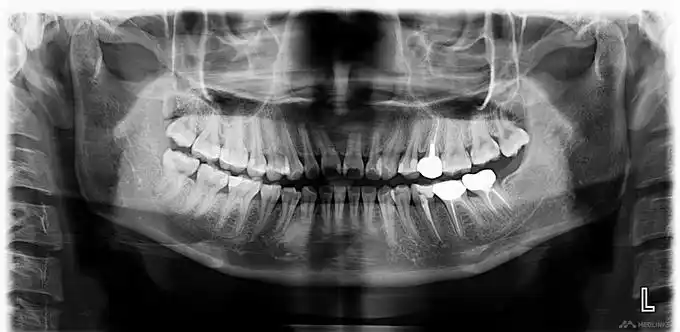

9张图教你如何看牙片#医学科普 - 抖音

【口腔图片有奖征集活动】-- 右上7根尖炎,重点是全景片很有意思(原创

上前牙窦道型慢性根尖周炎一例

左上前牙根尖周炎一例

左下后牙根尖周炎一例

根尖处这样大的阴影《附牙片》要怎么处理最好!